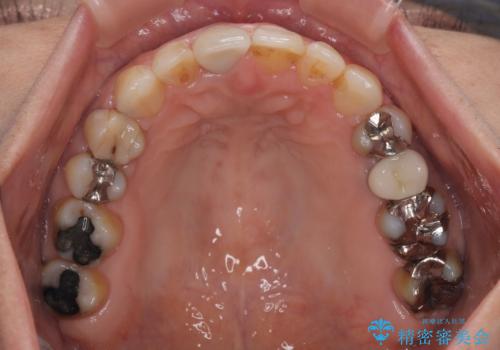

根管治療が必要な歯は事前に処置を行った上で矯正治療を開始し、概ね歯列が整ったところでセラミッククラウンなどに置き換え、その後インビザラインを1セット使用して仕上げていくこととしました。

痛みがなくなり歯列が整ったことで、残っている銀歯も気になり始めているようです。